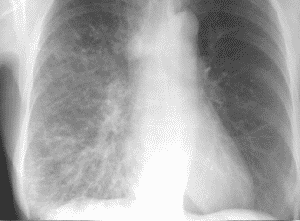

Linfangitis carcinomatosa